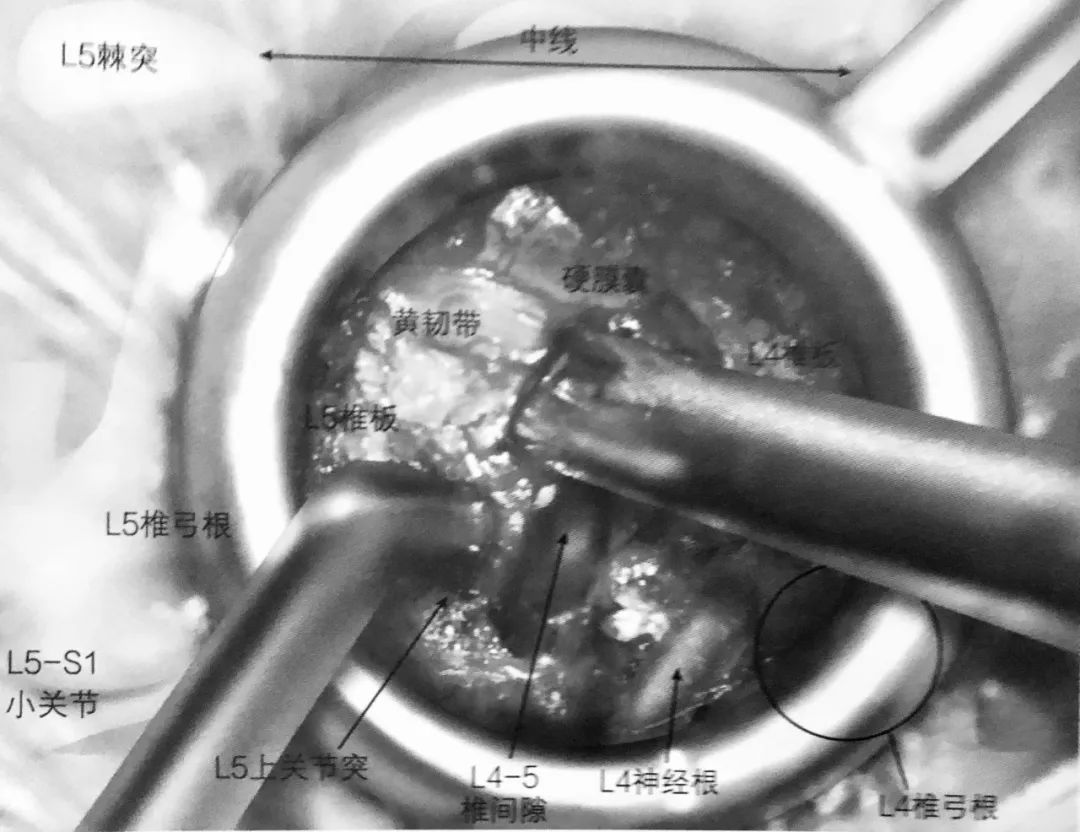

5. 一旦磨钻通过峡部,下关节突就可以去除,完成小关节切除术,显露病变椎间隙。

6. 切除黄韧带。最开始的时候要保留黄韧带,在实施减压时能起到保护硬膜囊的作用。

7. 应用双极电凝凝结椎间隙静脉丛止血。

8. 一旦完成静脉丛电凝止血,下位的椎弓根(L5)及 L4-5 椎间隙就能看得很清楚。L5 神经根中间部就在椎弓根内缘。L4 神经根出口就在椎间隙上缘,但并不一定需要显露。

9. 经椎间孔椎间融合术(TLIF)操作空间在椎间孔上位神经根出口的内侧。准备椎间植骨需要在侧位透视下进行。